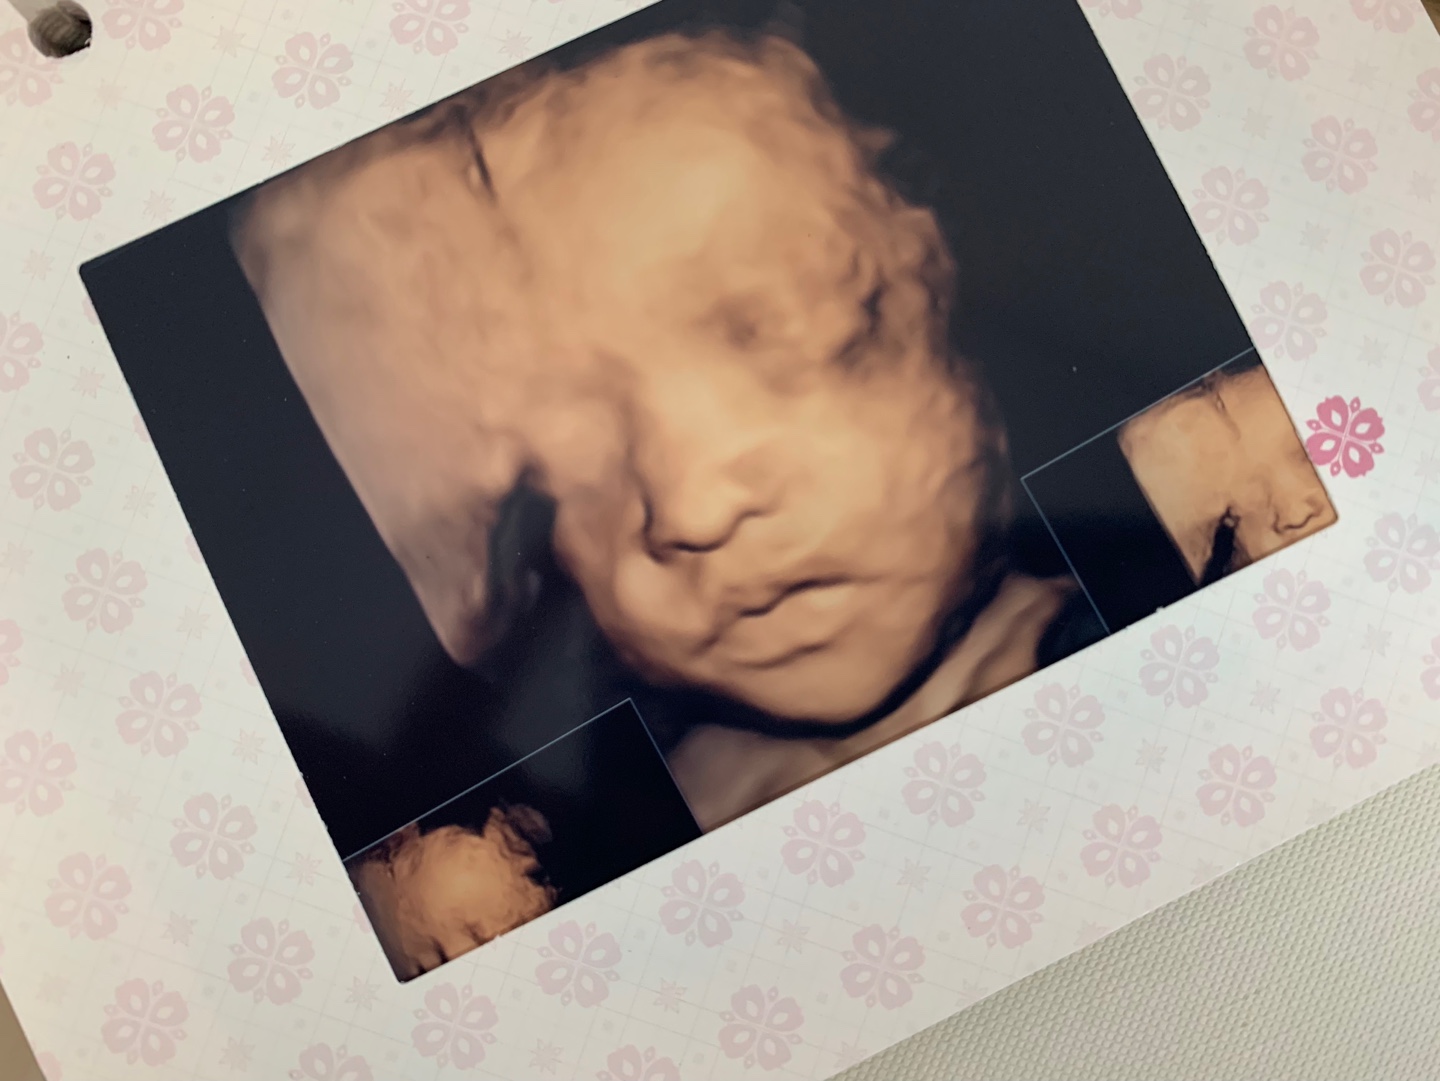

- 임신중기 정밀 초음파: 임신 중기에는 태아의 장기들이 어느정도 완성을 갖추게 되는 시기이므로 고해상도의 초음파를 이용하여 태아의 이상 유무를 확인합니다. 태아의 주요 장기가 이상 없이 잘 크고 있는지, 더불어 자궁 경부의 형태 및 길이도 함께 검사하여 조산의 위험성을 사전에 확인하기도 합니다. 초음파 검사를 통해 모든 이상의 유무를 완벽하게 진단할 수는 없지만 가능한 수준에서 관찰하고 그에 따른 계획을 미리 세울 수 있습니다.